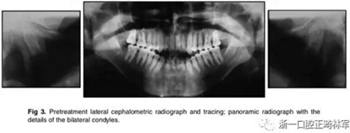

X片示:垂直向生長(zhǎng)過(guò)度,下頜后縮、上頜前突,上切牙前傾、前突,下切牙前突但唇舌向傾角正常;雙側(cè)髁突畸形,提示退行性變。

影像學(xué):全景片示:牙根平行度可。頭顱側(cè)位片及疊加圖示:下頜骨發(fā)生逆時(shí)針旋轉(zhuǎn),面部輪廓改善;上切牙轉(zhuǎn)矩正常,下切牙輕微舌傾;唇突度減小,鼻唇角增大。